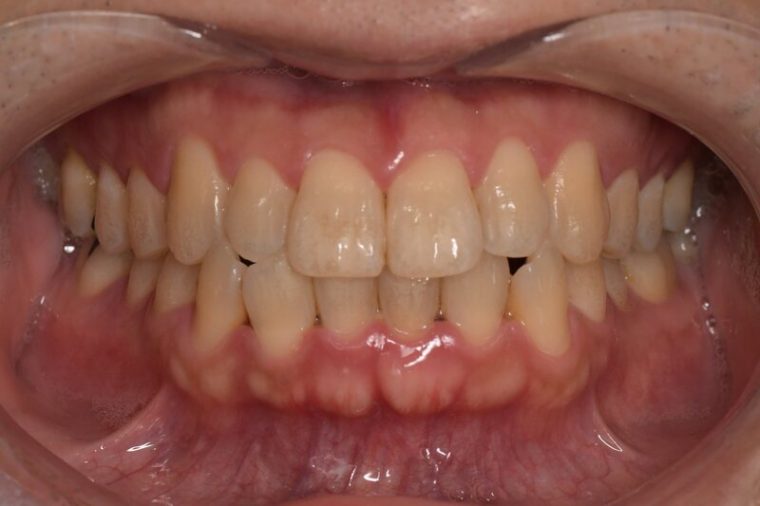

症例5

before

症例

after

歯周病検査(治療前)

歯周病検査(治療後)

レントゲン写真

基本情報

年齢・性別 32歳・男性

主訴 主訴:歯ぐきから出血する

治療部位:全顎

治療内容 「全顎」

歯周基本治療(歯周精密検査、スケーリング、OHI、SRP)

治療期間 約3ヶ月

治療費 歯周基本検査:約600円(保険診療3割負担)

スケーリング、OHI:約2,000円(保険診療3割負担)×2回

SRP、OHI:約1,500円(保険診療3割負担)×4回

歯周精密検査:約1,200円(保険診療3割負担)×2回

合計金額13,000円

(2025年2月現在)

治療方針 ①検査

レントゲン、口腔内写真を撮影して、歯や歯周組織の状態を確認します。

また、歯周病の検査で歯周ポケットの深さや出血の有無を確認します。

②スケーリング、OHI(口腔衛生指導)

スケーリングをして歯の表面の歯石を除去します。

また、正しい歯磨きの仕方や、フロスの通し方を一緒に確認します。

③歯周精密検査

前回歯石除去と歯磨き指導を行なった結果、歯ぐきの状態がどれぐらい改善したか検査します。

④SRP

歯ぐきの内側についてる歯石を除去します。

⑤歯周精密検査

SRP後、歯周病が改善されたか、検査します。

歯周ポケットが4ミリ以上の部位は、再度SRPを行います。

今回は歯周病の状態が安定したため、3ヶ月おきの定期検診で歯周病の再発や進行を防ぎます。

担当者所見 初診時は、写真を見て分かるように、歯ぐきが赤く腫れていました。

また、歯周病の検査では、全体的に歯と歯の間の部分の歯周ポケットが4ミリあり、全体の約81%から出血が認められました。

出血量も多く、歯ぐきに触れた瞬間に出血しました。

レントゲンで骨のレベルがしっかりとあることが確認できました。

そのため、ご自身で正しい歯磨きを継続することで改善すると考えました。

歯周基本治療を経て、再度検査した結果、歯周ポケットはほぼ3ミリ以下に改善しました。左下7番の残存した歯周ポケットは、隣の親知らずを抜いたため経過観察します。

出血率は約4%まで改善し、出血量も点状で少なくなりました。

今後は右上2番、右下3番の歯ぐきの発赤の改善と、出血率0%を目指して、定期検診でメンテナンスしていきます。